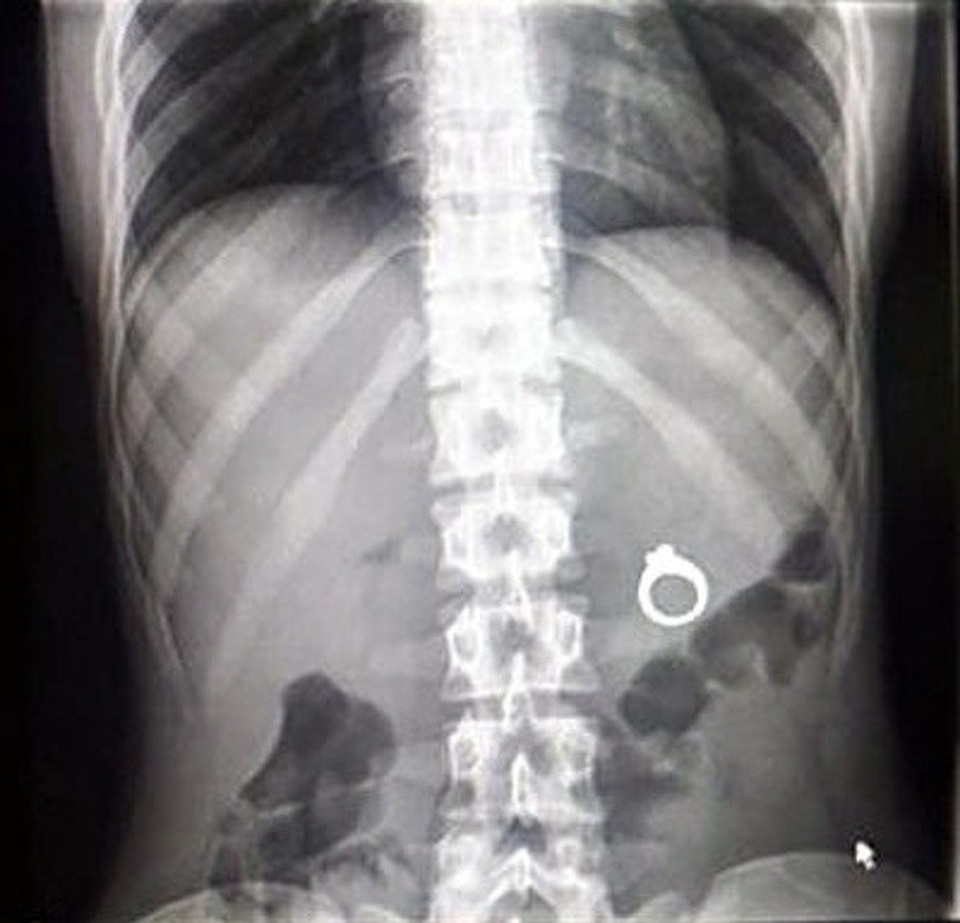

(Dân trí) - Hình ảnh chụp X-quang của những chủ thể đặc biệt như: một chú mèo đang mang thai, bộ phận cơ thể bị dị tật bẩm sinh hay thậm chí là bụng của cô bé nuốt nhầm chiếc bấm móng, được tổng hợp dưới đây, sẽ giúp bạn như bước vào một thế giới mà mình chưa từng biết!